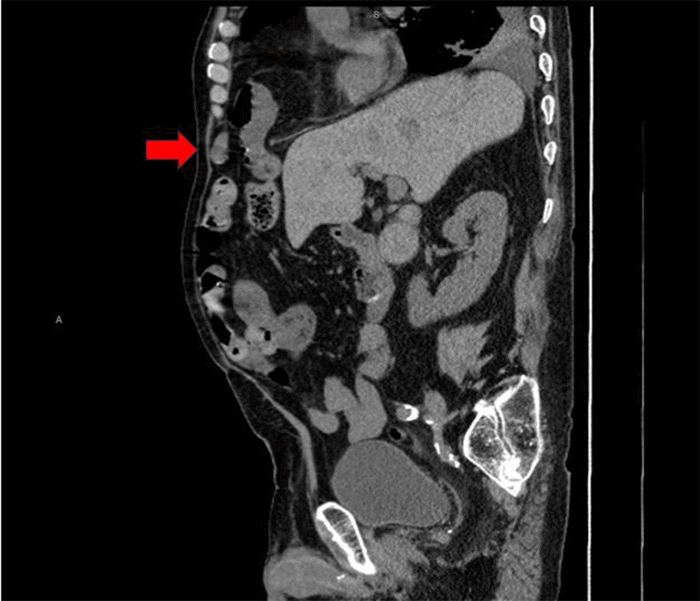

Figure 5. Sagittal Computed Tomography View of Morgagni Hernia. Published with Permission

Sagittal reformatted view from a CT scan of the abdomen. This image clearly displays the anteriorly positioned diaphragmatic defect characteristic of a Morgagni hernia, with loops of small bowel and omentum (red arrow) seen protruding superiorly through the diaphragm

On physical exam, the patient was afebrile and hemodynamically stable. His abdomen exhibited mild RUQ tenderness on palpation; however, Murphy’s sign was absent, and there was no rebound tenderness or guarding. Initial laboratory evaluation revealed a mild anemia, while aminotransferase, alkaline phosphatase, and lipase levels were within normal limits. A computed tomography angiogram (CTA) of the abdomen and pelvis re-demonstrated significant gallbladder distension and showed non-enhancing, hyperdense material consistent with a large blood clot occupying approximately 75% of the gallbladder lumen, diagnostic of hemorrhagic cholecystitis (Figure 3). Additionally, a right-sided anterior diaphragmatic hernia, consistent with a Morgagni hernia, was incidentally found, containing omentum and loops of small bowel without evidence of obstruction (Figures 4 and 5). By the second day of admission, repeat laboratory tests showed a new elevation in liver enzymes (AST 130 IU/L, ALT 101 IU/L, alkaline phosphatase 250 IU/L) and a decline in hemoglobin from 10.7 to 9.0 g/dL. Following a multidisciplinary conference involving hematology, neurology, and perioperative care services, a decision was made to proceed with urgent surgical intervention.